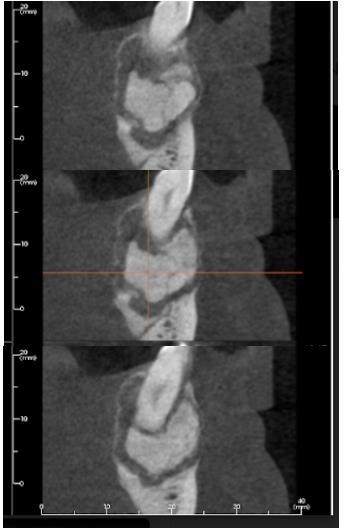

En la radiografía panorámica se observaron estructuras óseas difuminadas en el sector posteroinferior izquierdo mandibular con una lesión radiolúcida, bien circunscrita, en un espacio de 3,8 * 6,3 cm, con presencia de radiopacidades centrales, encapsulada y de bordes definidos. Se distinguían los dientes permanentes formados y levemente desplazados hacia lingual. En el análisis tomográfico se evidenció imagen hiperintensa localizada en el tercio apical del segundo premolar inferior izquierdo, de aproximadamente 3 cm de diámetro, rodeada por una zona hipointensa con compromiso de la tablas mandibulares (figura 2).